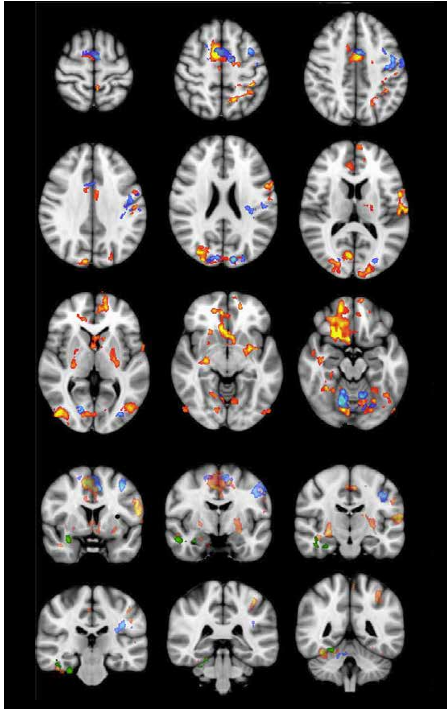

Der EEG måler elektrisk nervecelleaktivitet i store delområder av hjernebarken, kan avan serte hjerneavbildningsteknikker visualisere både struktur og aktivitet i alle deler av hjernen, ned til i ganske små delområder. En av de mest kjente metodene er fMRI, hvor man bruker en MR-maskin til å vise endringer i hjernevevets stoffskifteaktivitet. Under Acem-meditasjon hadde deltagerne høyere aktivitet i både pre frontal cortex og hippocampus enn i hvile. Disse områdene av hjernen arbeider henholdsvis med overordnet innsikt og forståelse og med hu kommelse. Nærmere analyse av disse funnene viste dessuten at hjernens hvilenettverk (de fault mode network) ble sterkere aktivert under Acem-meditasjon enn ved vanlig hvile. Dette nettverket er ansvarlig for fri tankevandring, også beskrevet som spontanaktivitet i Acem meditasjon. Denne type hjerneaktivitet er det lite av ved konsentrasjon..

9. Davanger S, Ellingsen O, Holen A, Hugdahl K. Meditation-specific prefrontal cortical activation during acem meditation: an fMRI study. Percept Mot Skills. 2010;111(1):291-306.

10. Xu J, Vik A, Groote IR, Lagopoulos J, Holen A, Ellingsen O, et al. Nondirective meditation activates default mode network and areas associated with memory retrieval and emotional processing. Front Hum Neurosci. 2014;8:86.

11. Engstrom M, Pihlsgard J, Lundberg P, Soderfeldt B. Functional magnetic resonance imaging of hip pocampal activation during silent mantra meditation. J Altern Complement Med. 2010;16(12):1253-8.